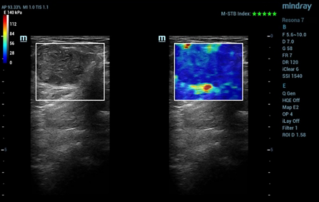

Female pelvic floor anatomy, which developed since the early 20th century, has had a variety of theories, including integral theory, three levels of vaginal support theory, "hammock hypothesis", and three-chamber system. Supporting structures such as pelvic floor muscles, fascia and ligament play an important role in maintaining the normal function of pelvic floor, among which levator ani muscle group is one of the most important supporting structures.